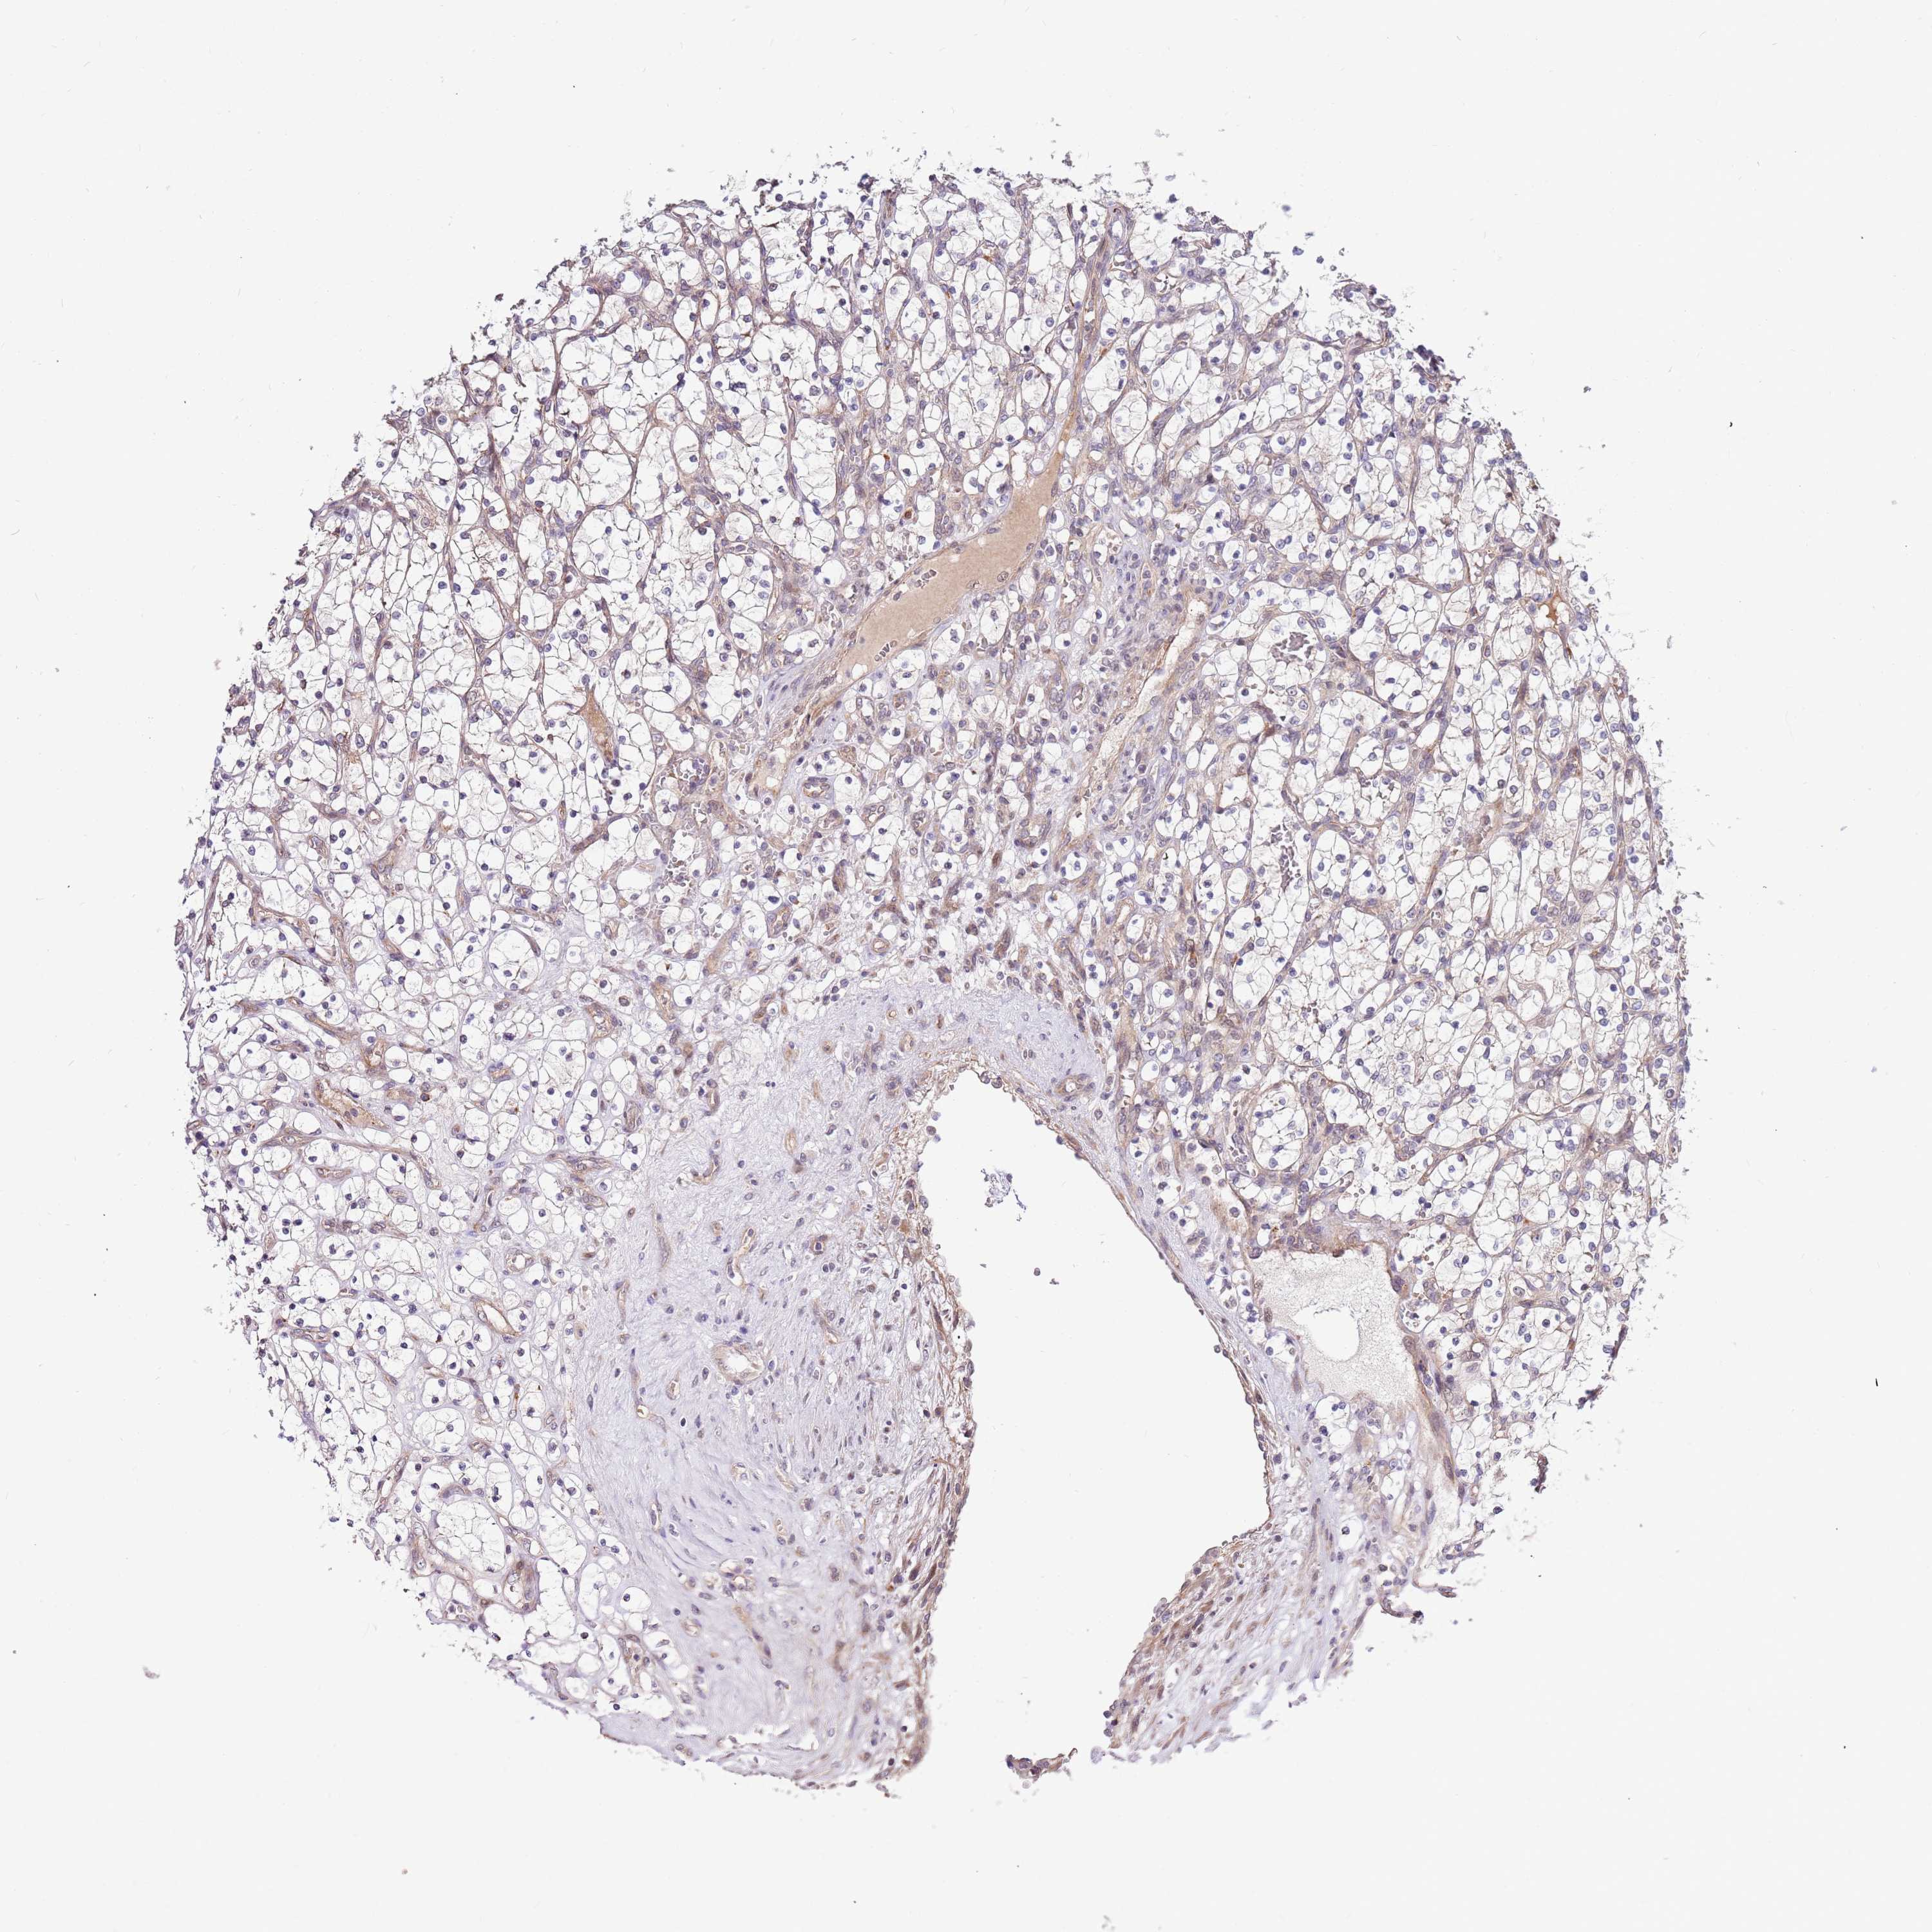

CANCER RENAL CANCER Show tissue menu

KICH TCGA KIRC TCGA KIRC VALIDATION KIRP TCGA PROTEIN RCC CPTAC PROTEIN EXPRESSION